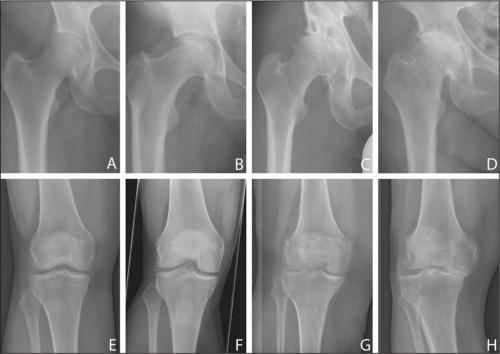

Все медикаментозные средства эффективны лишь на I—II стадиях артроза, но бессильны на III и IV. Если в патологию вовлечены не только суставы, но и кости, никакой препарат не поможет. В этом случае избавиться от хронических болей в суставах, трудностей при ходьбе, ограниченной подвижности суставов и других неприятных симптомов можно только с помощью операции.

При артрозе истончается хрящевая соединительная ткань сустава, тем самым травмируя кости